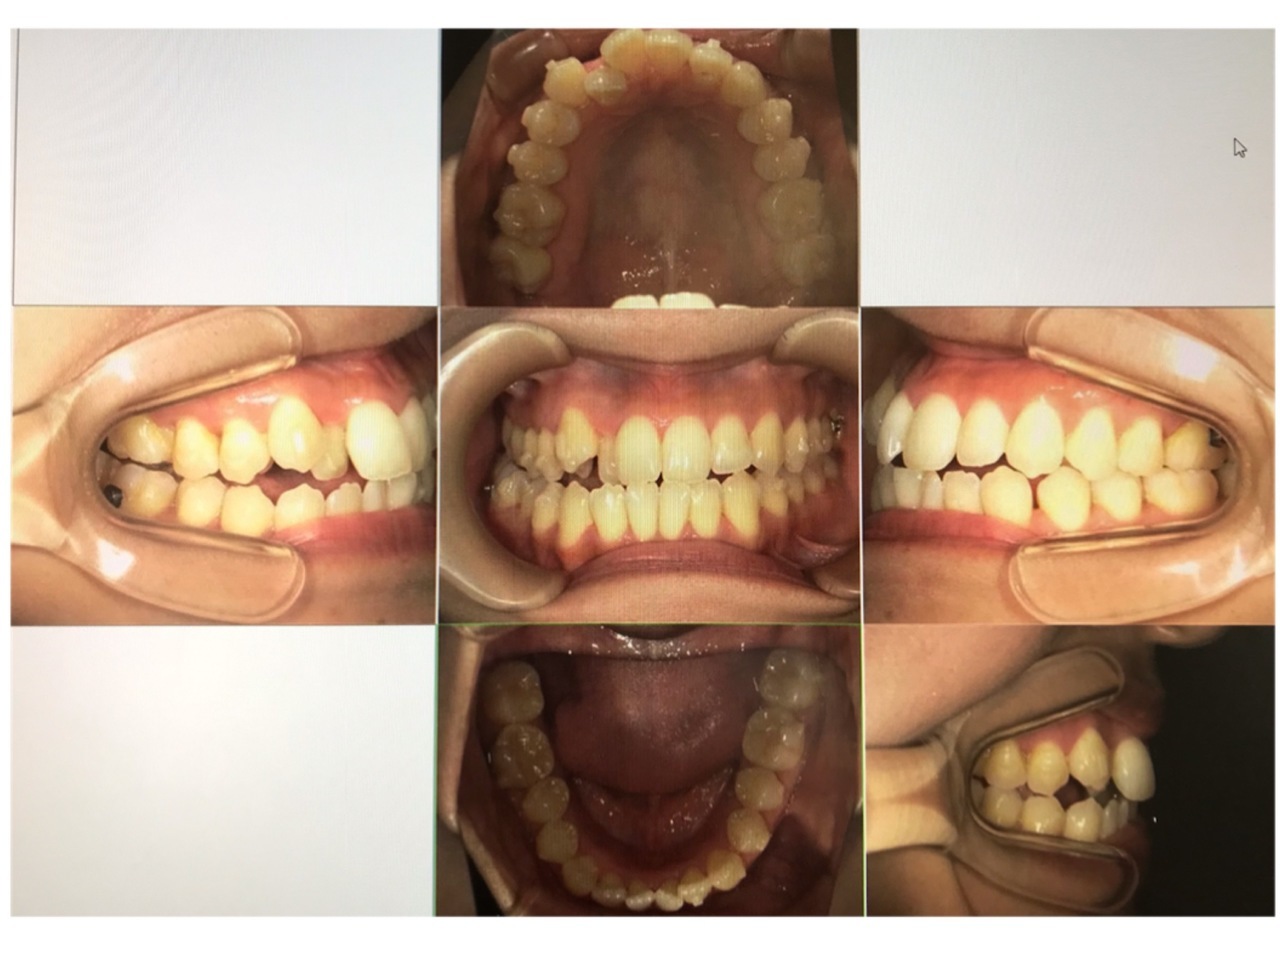

スタッフのインビザラインの経過です!

23枚目に入りました。

奥歯のスペースがとても広がってきました。

一度の食事でかなり食べ物が隙間に入るので、毎食後のブラッシングにはフロスも必需品です。